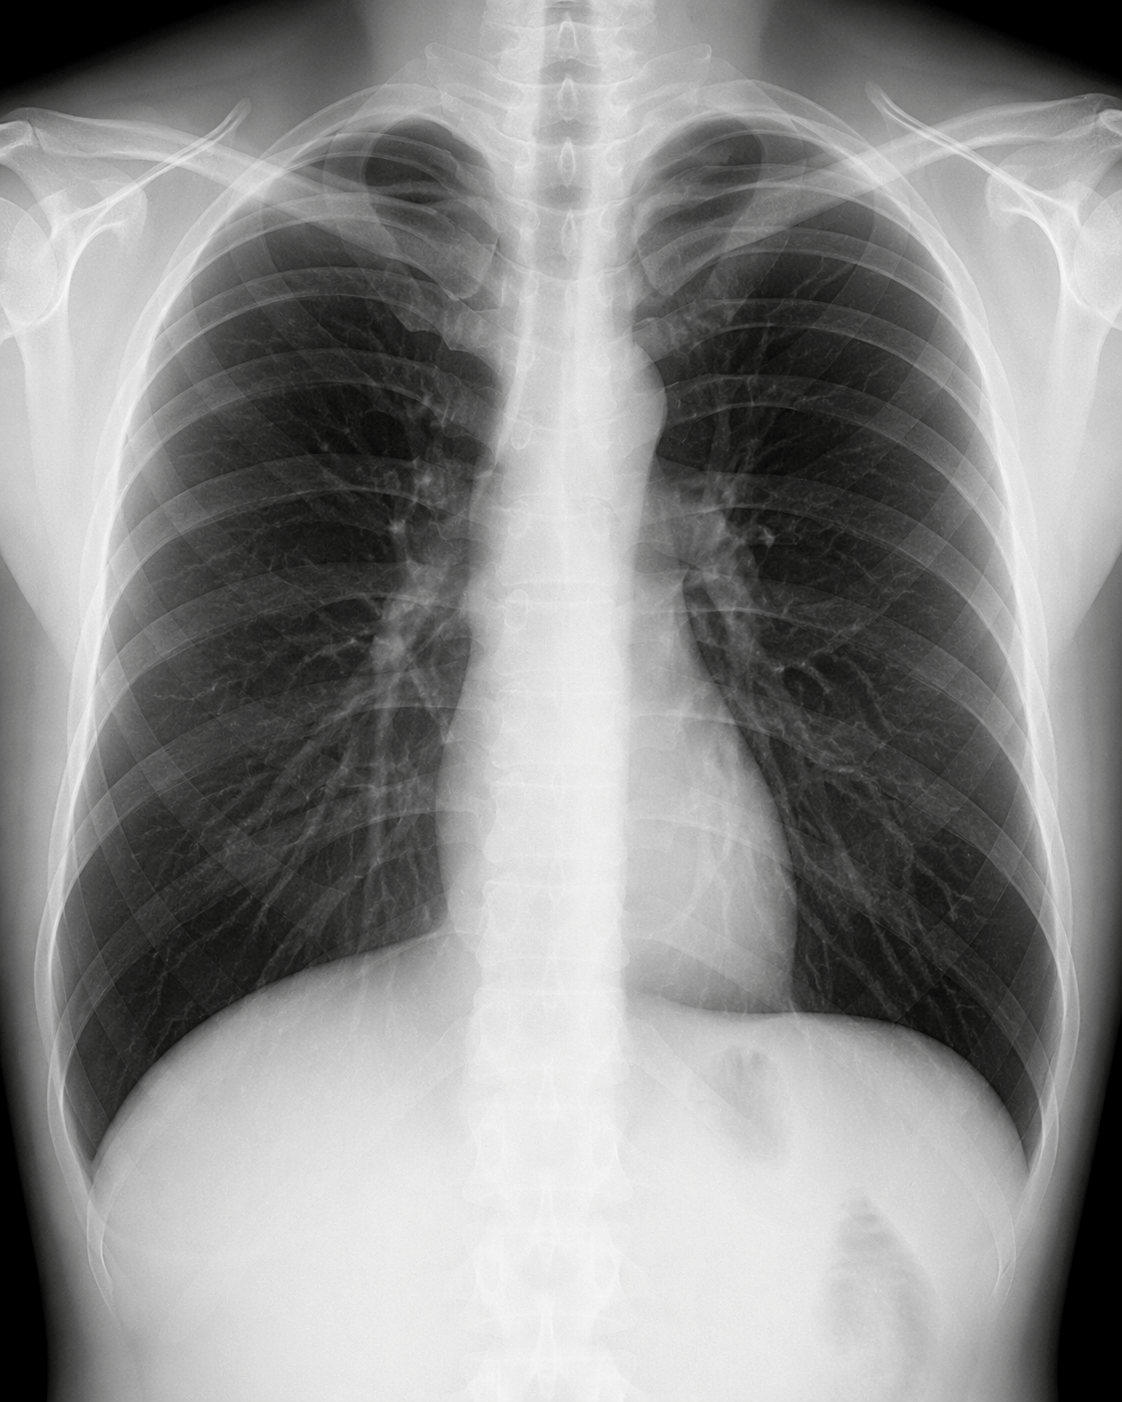

胸部X線検査

胸部のレントゲン検査です。肺炎、気胸、胸水、心拡大などの評価に加え、長引く咳や息苦しさの原因検索にも用います。喘息が疑われる場合でも、他の呼吸器疾患が隠れていないか確認するために行うことがあります。必要に応じて、副鼻腔や腹部などの撮影にも対応します。